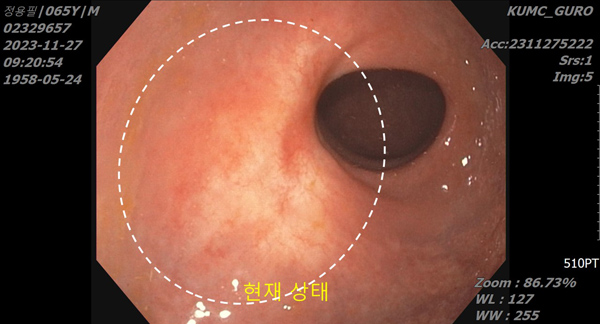

In April of 2024, I underwent comprehensive medical test including blood test, endoscopy, MRI, and CT. After the examination, the doctor said in surprise, ŌĆ£Oh! No more cancerous tissue at all! I canŌĆÖt see any traces or roots.ŌĆØ

I came to a realization that my rectal cancer and all cancerous cells were burned away by the prayers from Senior Pastor Soojin Lee and the late Director Boknim Lee. Hallelujah!

There are a few acquaintances who wear diapers due to side effects of rectal cancer surgery. I was healed of my rectal cancer without surgery and have been healthy for one year and 10 months. I am so grateful for the grace and love of God the Father.

No more cancerous tissue